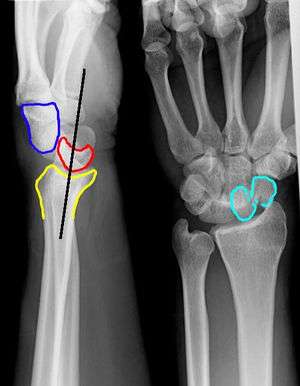

Perilunate Dislocation

Perilunate Dislocation

- Lateral view

- Capitate displaced dorsal to lunate

- Lunate retains its normal contact with radius

- PA view

- Capitolunate joint space is obliterated as the bones overlap one another

Lunate Dislocation

- Lateral view

- Lunate is pushed off the radius into the palm ("spilled teacup" sign)

- PA view

- Lunate has triangular shape ("piece-of-pie sign")